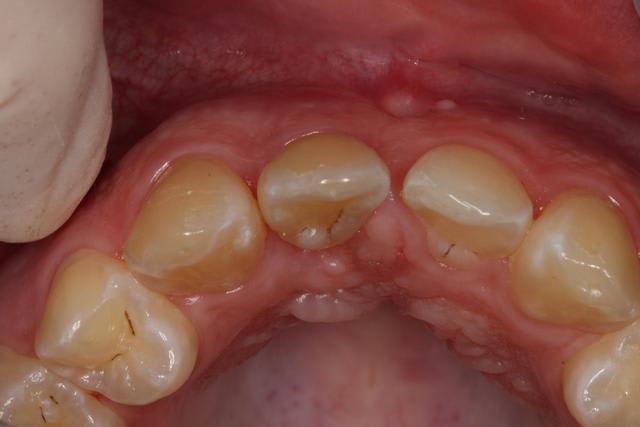

06/01/2012 à 01h26

Provisoires

Gencive légèrement moins galbée sur implant

06/01/2012 à 01h42

joli...;-)

mais tu devrais un poil augmenter l'épaisseur au collet en épaississant le composite...çà va refouler ta gencive en vestibulaire et comme en même temps çà va la faire remonter un peu, tu auras les collets plus alignés...;-)

dommage en tout cas, ton implant, un tout petit peu plus enfoui et çà aurait été parfait...

+1 et élargi la face mésiale de 11 pour avoir un profil de la papille centrale plus symétrique